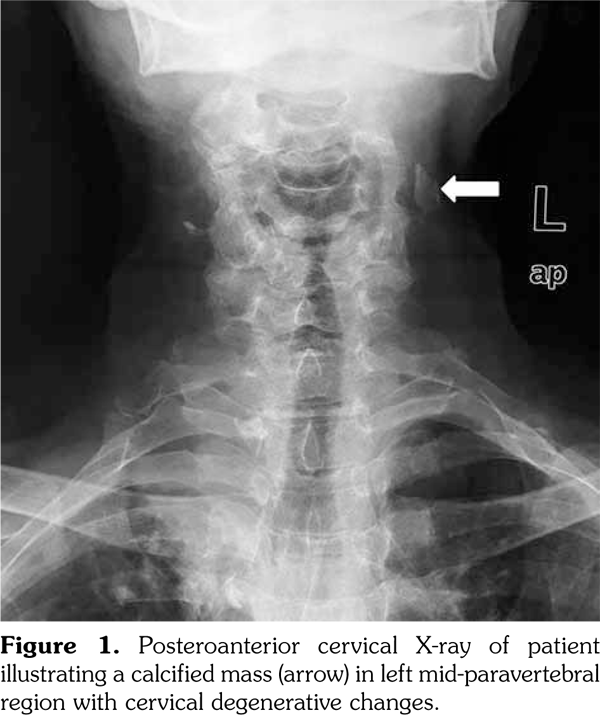

An 80-year-old female patient was examined due to complaint of neck pain over the last year which has aggravated recently. She denied history of trauma. Her medical history indicated that she was taking some medications for hypertension and coronary artery disease. Physical examination was compatible with cervical osteoarthritis with limited cervical range of motion in all directions and tenderness to palpation. Laboratory findings including complete blood count, erythrocyte sedimentation rate, C-reactive protein, serum calcium, phosphorus, parathyroid hormone, and vitamin D levels were within normal ranges. On radiological evaluation, cervical X-ray revealed a calcified mass in the left mid-paravertebral region with cervical degenerative changes (Figure 1). At first glance, a calcification inside the cervical muscles was suspected. Ultrasonographic examination of the cervical region revealed the presence of intraluminal calcification at the level of the bifurcation of the left common carotid artery (Figure 2a-c). The patient was referred to neurology department for being at risk for stroke.